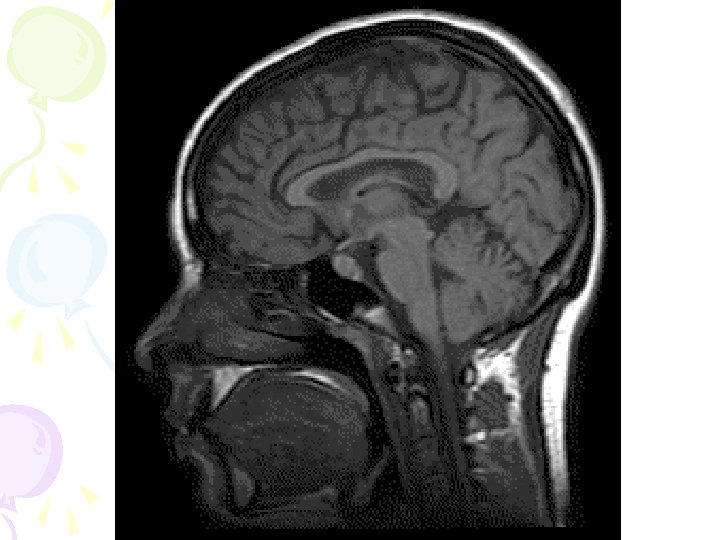

Magnetic Resonance Imaging (MRI) • A technique that uses magnetic fields and radio waves to produce computer-generated images that allow us to see structures within the brain